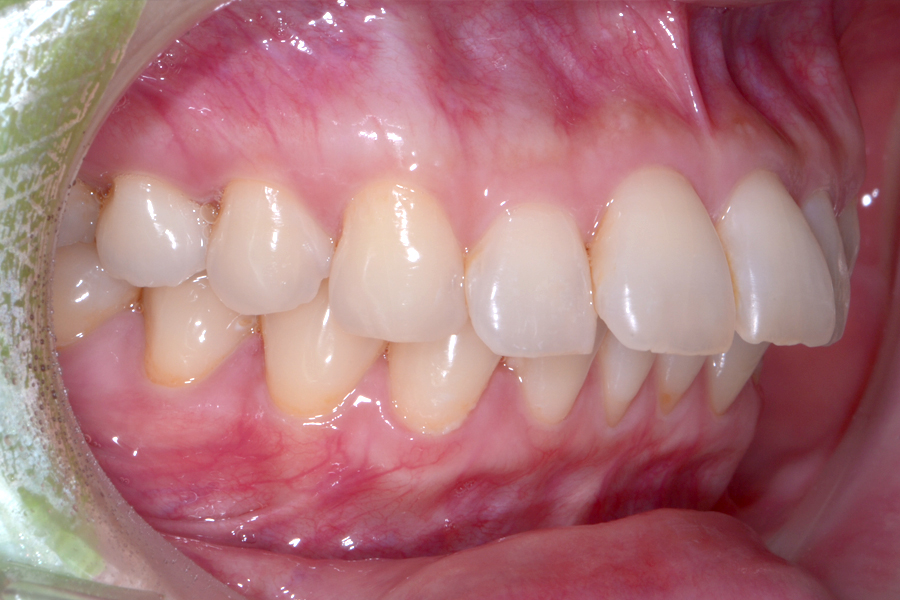

• 治療前